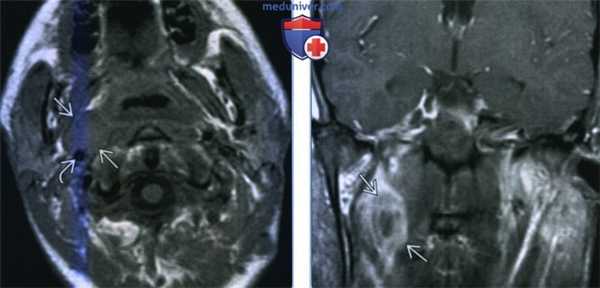

(Слева) МРТ Т1ВИ, аксиальная проекция. Медиальнее от правой внутренней сонной артерии располагается мягкотканное образование, представляющее собой увеличенный заглоточный лимфоузел. Обратите внимание, что, несмотря на свои размеры, лимфоузел никак не деформирует контуры глотки, поэтому при осмотре увидеть его невозможно. В прошлом пациент перенес апластическую анемию и трансплантацию костного мозга.

(Справа) МРТ Т1ВИ с КУ, коронарная проекция, этот же пациент. Вокруг лимфоузла отмечается кольцо накопления контраста, внутри него - зона некроза. У пациента диагностирована посттрансплантационная неходжкинская лимфома.